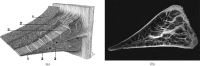

A variety of techniques are now available to directly or indirectly detect signal from tissues, fluids and materials that have short, ultrashort or supershort T₂ or T₂* components. There are also methods of developing image contrast between tissues and fluids in the short T₂ or T₂* range that can provide visualisation of anatomy, which has not been previously seen with MRI. Magnetisation transfer methods can now be applied to previously invisible tissues, providing indirect access to supershort T₂ components. Particular methods have been developed to target susceptibility effects and quantify them after correcting for anatomical distortion. Specific methods have also been developed to image the effects of magnetic iron oxide particles with positive contrast. Major advances have been made in techniques designed to correct for loss of signal and gross image distortion near metal. These methods are likely to substantially increase the range of application for MRI.